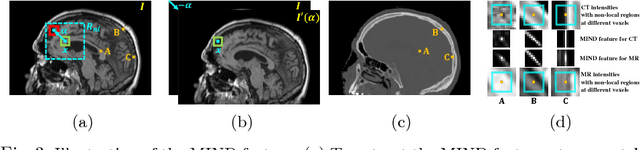

Abstract:The cycleGAN is becoming an influential method in medical image synthesis. However, due to a lack of direct constraints between input and synthetic images, the cycleGAN cannot guarantee structural consistency between these two images, and such consistency is of extreme importance in medical imaging. To overcome this, we propose a structure-constrained cycleGAN for brain MR-to-CT synthesis using unpaired data that defines an extra structure-consistency loss based on the modality independent neighborhood descriptor to constrain structural consistency. Additionally, we use a position-based selection strategy for selecting training images instead of a completely random selection scheme. Experimental results on synthesizing CT images from brain MR images demonstrate that our method is better than the conventional cycleGAN and approximates the cycleGAN trained with paired data.